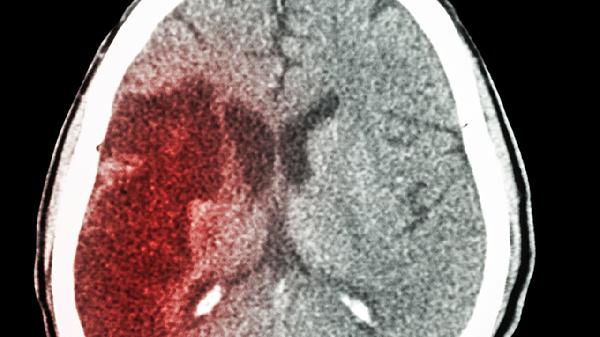

4、影像学表现不同

头颅MRI检查中,脱髓鞘病变多显示脑室周围白质T2高信号病灶,病灶与血管分布无关。脑梗塞在DWI序列呈现高信号,ADC图低信号,病灶分布符合血管供血区。增强扫描时,活动期脱髓鞘病灶可出现开环样强化,脑梗塞多呈脑回样强化。